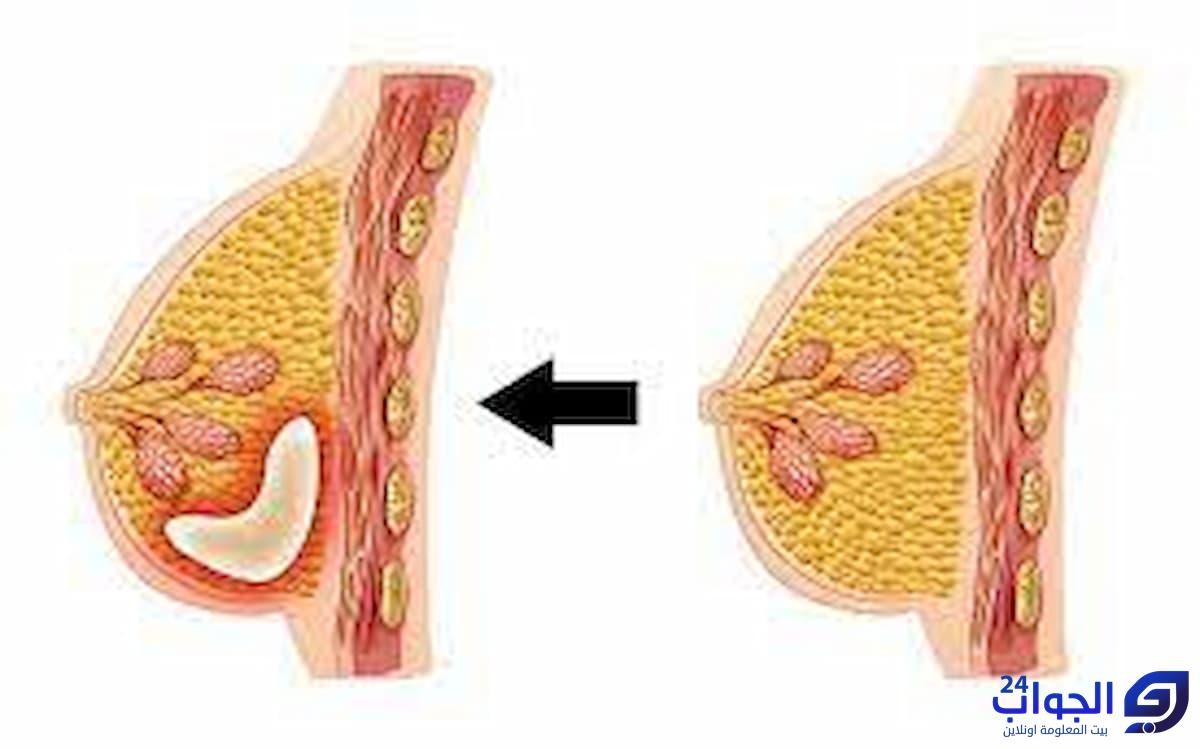

روت إحدى السيدات أن لها تجربتها مع سيدوفاج في تحقيق حلم الحمل، حيث كانت تعاني من المشكلة الصحية التي يطلق عليها تكيس المبايض، وهو ما جعلها تعاني من العقم بسبب مشاكل الإباضة، وكانت تعاني من دورة شهرية غير منتظمة بسبب تلك المشاكل، وعندما وصف أحد الأطباء المتابعين لحالتها عقار سيدوفاج الذي يستخدم بصورة واسعة في علاج مشكلة تكيس المبايض تمكنت من الإنجاب بعد فترة من تلقي العلاج.

وتجدر الإشارة إلى أن دواء سيدوفاج يساعد جسم المرأة على تحفيز التبويض لديها، ولهذا السبب يتم وصفه من أجل علاج المشكلة الصحية المعروفة باسم متلازمة تكيس المبايض.

- كما يشتهر وصف هذا الدواء في حالات تكيس المبايض؛ لأنه يعزز من عملية تحفيز التبويض لدى المرأة التي تعاني من مشكلة تكيس المبايض التي ينتج عنها حالات من العقم لدى الكثير من السيدات.